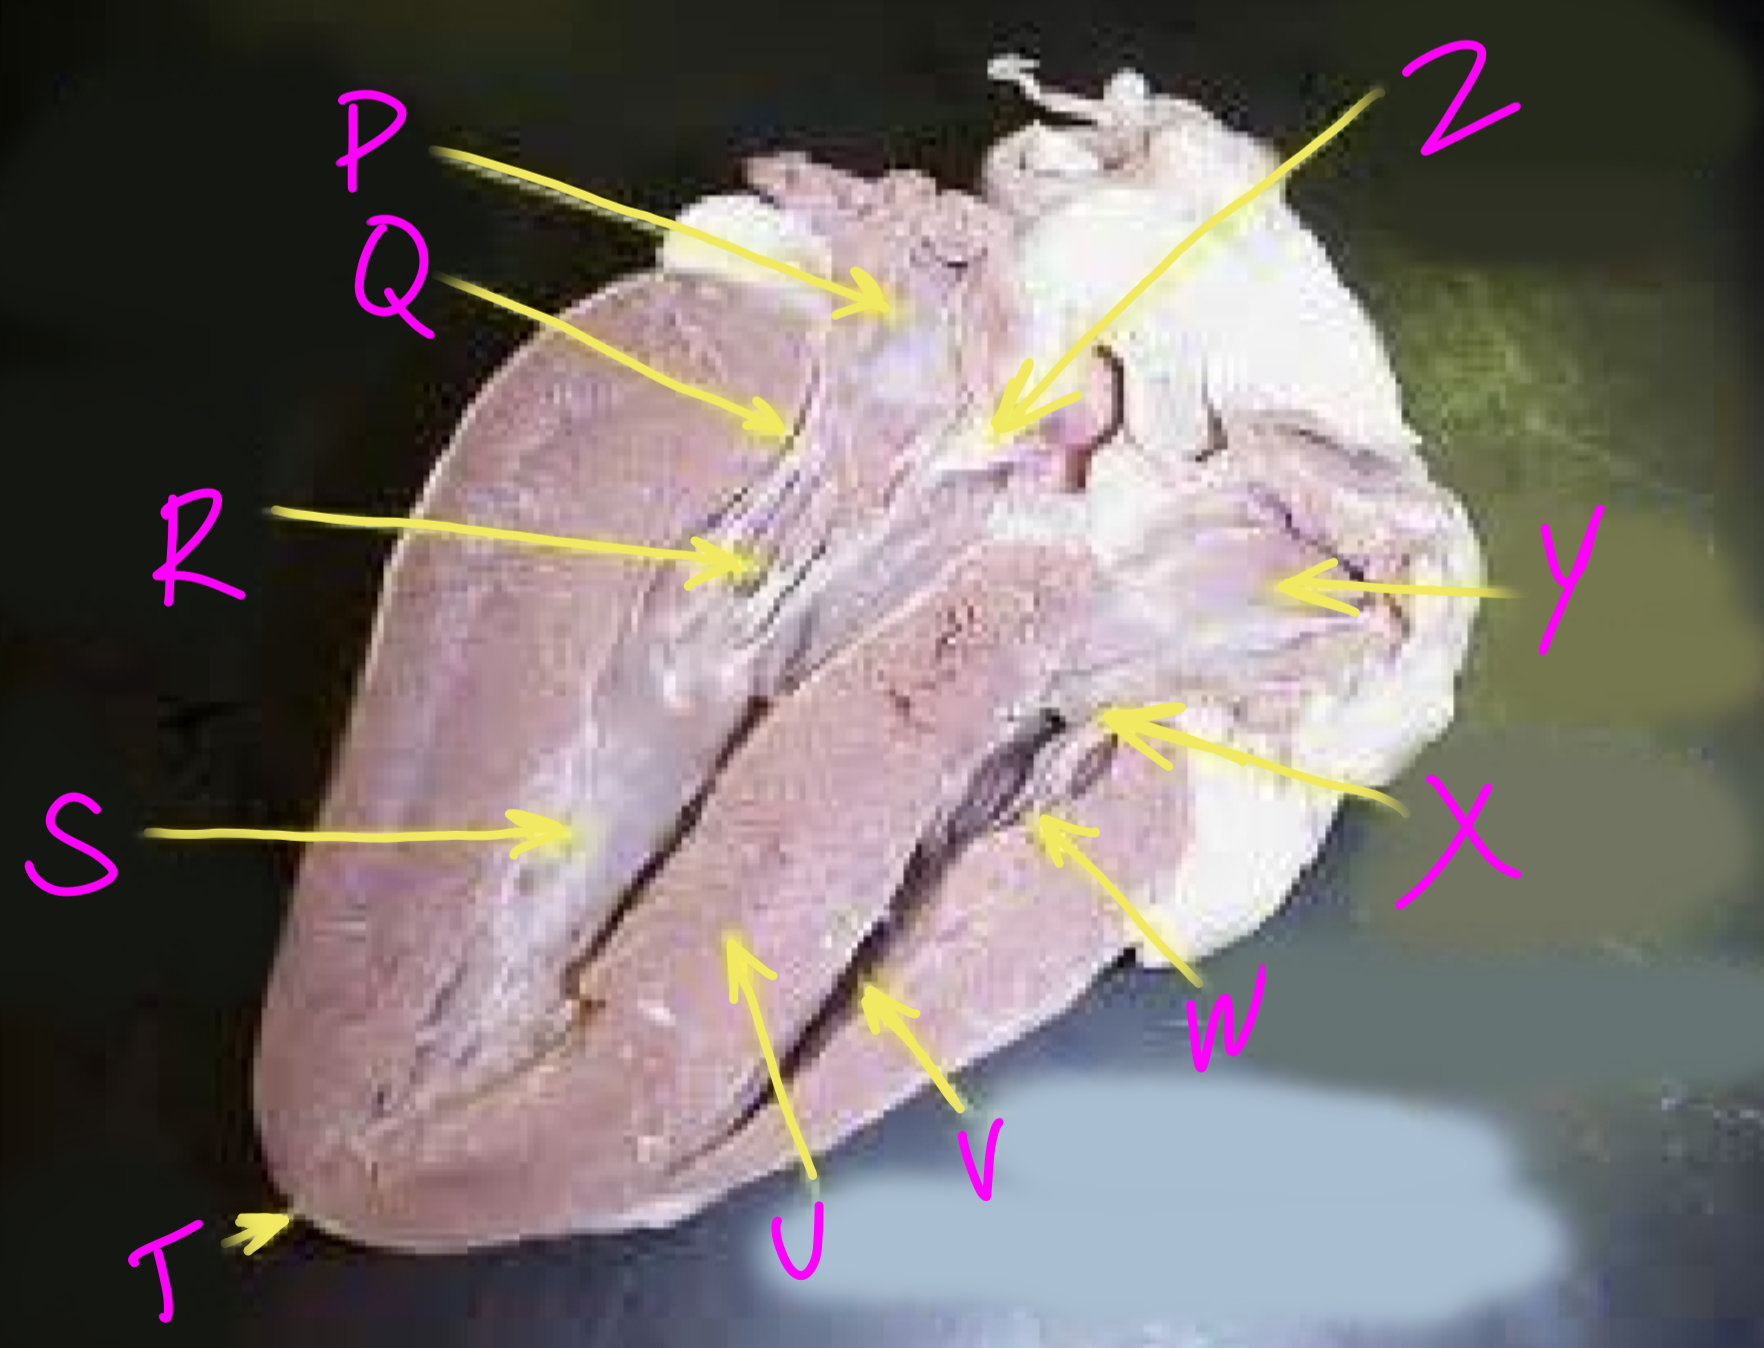

P

Left atrium

Q

Bicuspid valve - allows blood to flow from the left ventricle to the aorta

R

Right chordae tendinae - hold AV valves in place

S

Left ventricle

T

Apex - pumps blood out of the ventricles

U

Interventricular septum - divides the right and left ventricles

V

Right ventricle

W

Left chordae tendinae - hold AV valves in place

X

Tricuspid valve

Y

Right atrium

Z

Aortic semilunar valve - prevent backflow